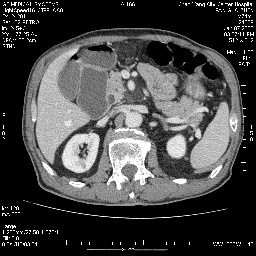

壶腹部的占位性病变,考虑为十二指肠癌并梗阻,但脾内多发性低密度区为转移吗?

还有胃、脾之间可见有侧支循环建立。左肾盂积水。

考虑来源于十二指肠水平段的恶性占位,侵及周围组织,特别是胰腺,可见区域淋巴结肿大,左侧下腔静脉畸形。

病变主要位于钩突(癌)。如是壶腹部,肝内外胆管扩张明显。